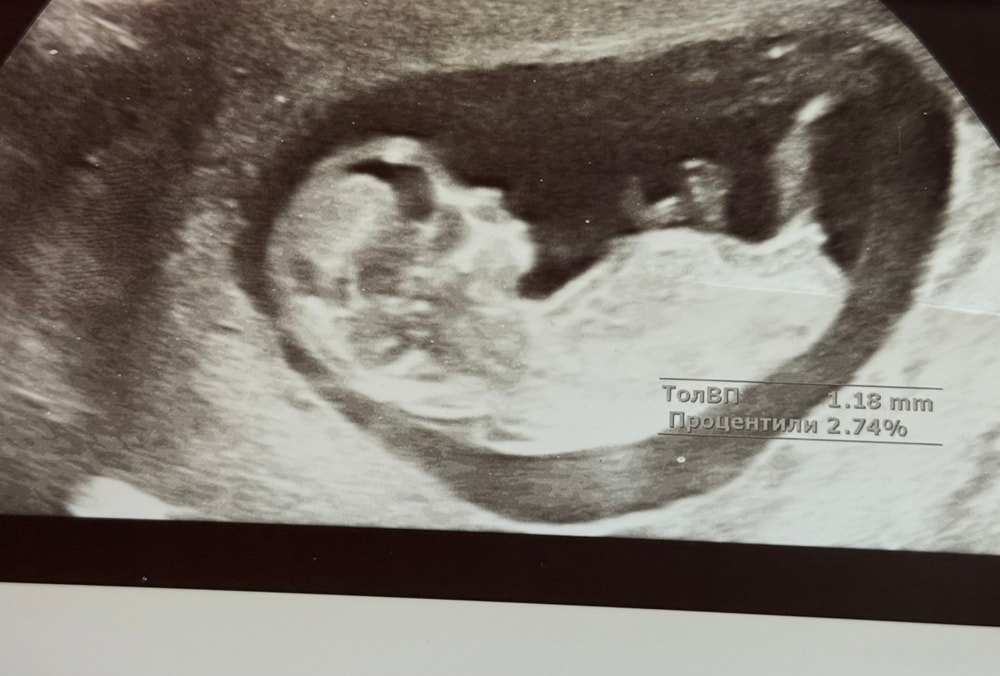

УЗИ, КТГ, доплерЗдравствуйте, милые девочки. Сходила на УЗИ 15,3. Кого вы видите?😁

Узист прям уверен на 100%😁